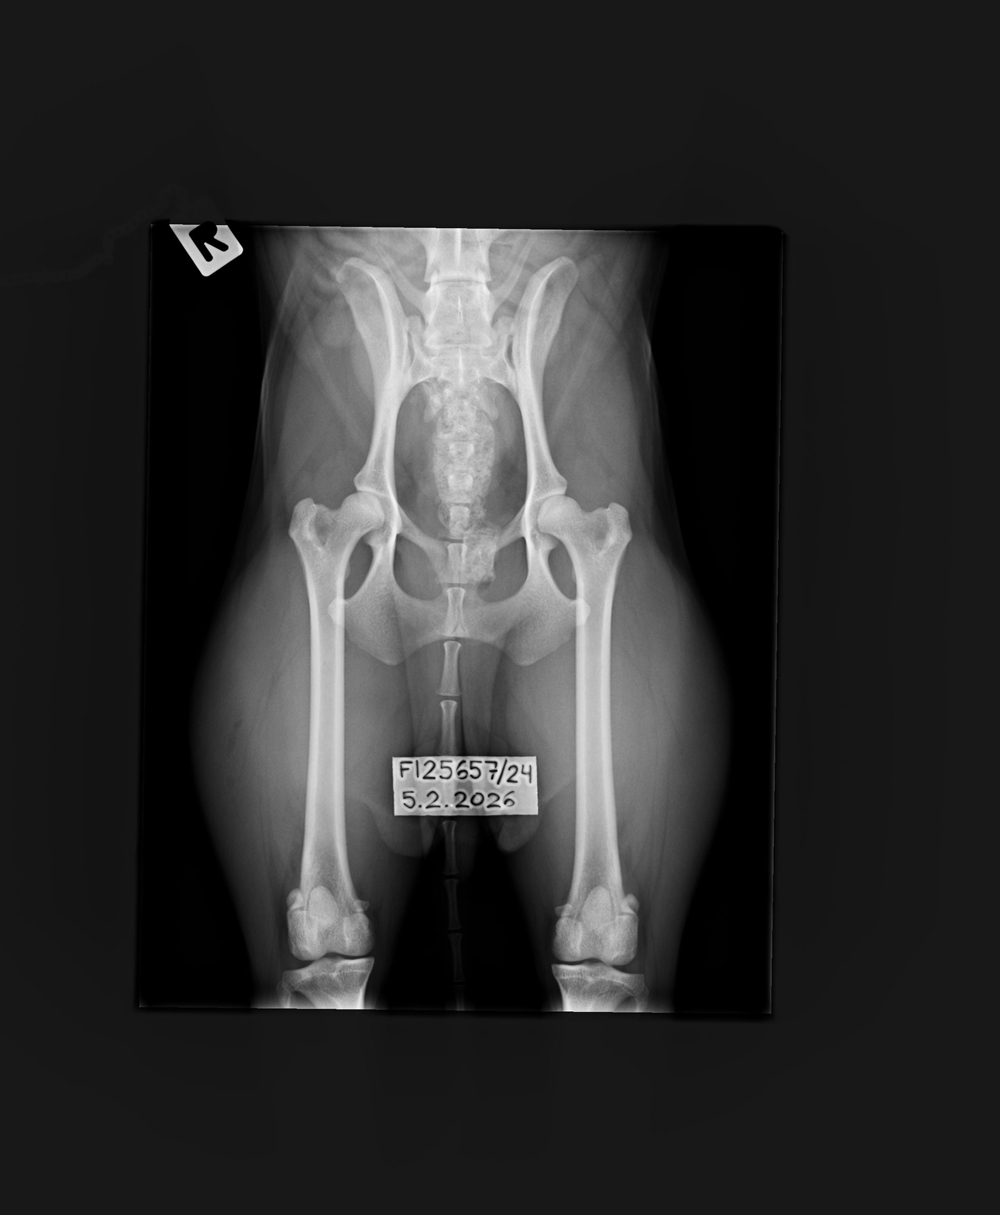

NHAT Pihlajamäen Aslan ♂ Personal

page - KoiraNet |

Clear Sep '25 |

C/B |

1/0 (see Notes) |

0/0 |

Normal Sep '25 |

Carrier (at-home swab) |

Clear by parentage |

- |

- Degenerative Myelopathy Normal/Carrier (Embark at-home swab)

- ift122-PRA Normal/Clear (Embark at-home swab)

- Canine Multifocal Retinopathy (CMR) Normal/Clear (Embark at-home swab)

- Lundehund syndrome Normal/Carrier (Embark at-home swab)

- Genetic COI 0 % (Embark)

- Finnish Kennel Club's elbow x-ray report Dec '25: Signs suggestive of medial coronoid disease; further information about the condition of the joints can be obtained, if necessary, by computed tomography (CT) examination

- Finnish Kennel Club's elbow CT report Feb '26: A small amount of new bone formation around the medial coronoid process of the left elbow

- Shoulder osteochondritis: Unaffected/Unaffected

- Free of lumbosacral transitional vertebrae (LTV0)

- Free of spondylosis (SP0)

- Free of vertebral anomalies (VA0)

- Spine x-rays: 1, 2 ja 3

- Sheep herding aptitude test

passed '24

- Reindeer herding aptitude

test passed '25

- Temperament tested +155

points/gun-sure